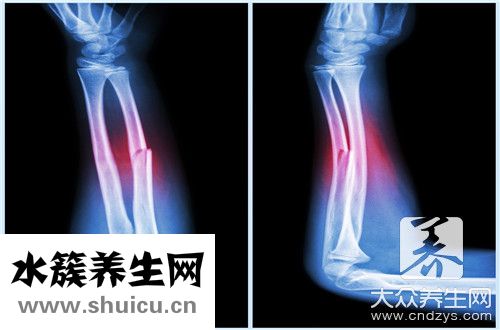

肱骨是人體中上肢最大的骨骼,肱骨上端是構成肩關節的重要部分,肱骨下端是構成肘關節的部位,但肱骨出現骨折的概率也非常高,一般與個人行為有關,老年人群骨骼...

(0) 0的病因一般有3種,分別為直接暴力、間接暴力和旋轉暴力。 直接暴力是橫行骨折或粉碎性骨折,有時也可發生多級骨折。 間接暴力多為斜行骨折,該骨折易刺傷肌肉,旋轉暴力可引起典型的螺旋狀骨折。 )...

如果對人體施加外力,則可能為肱骨近端骨折。 通過檢查,如果肱骨的大骨頭沒有大問題,骨折的程度也較輕,則可以選擇保守的治療。 病情嚴重的話,不能遲到。 需要立即通過手術進行治療...